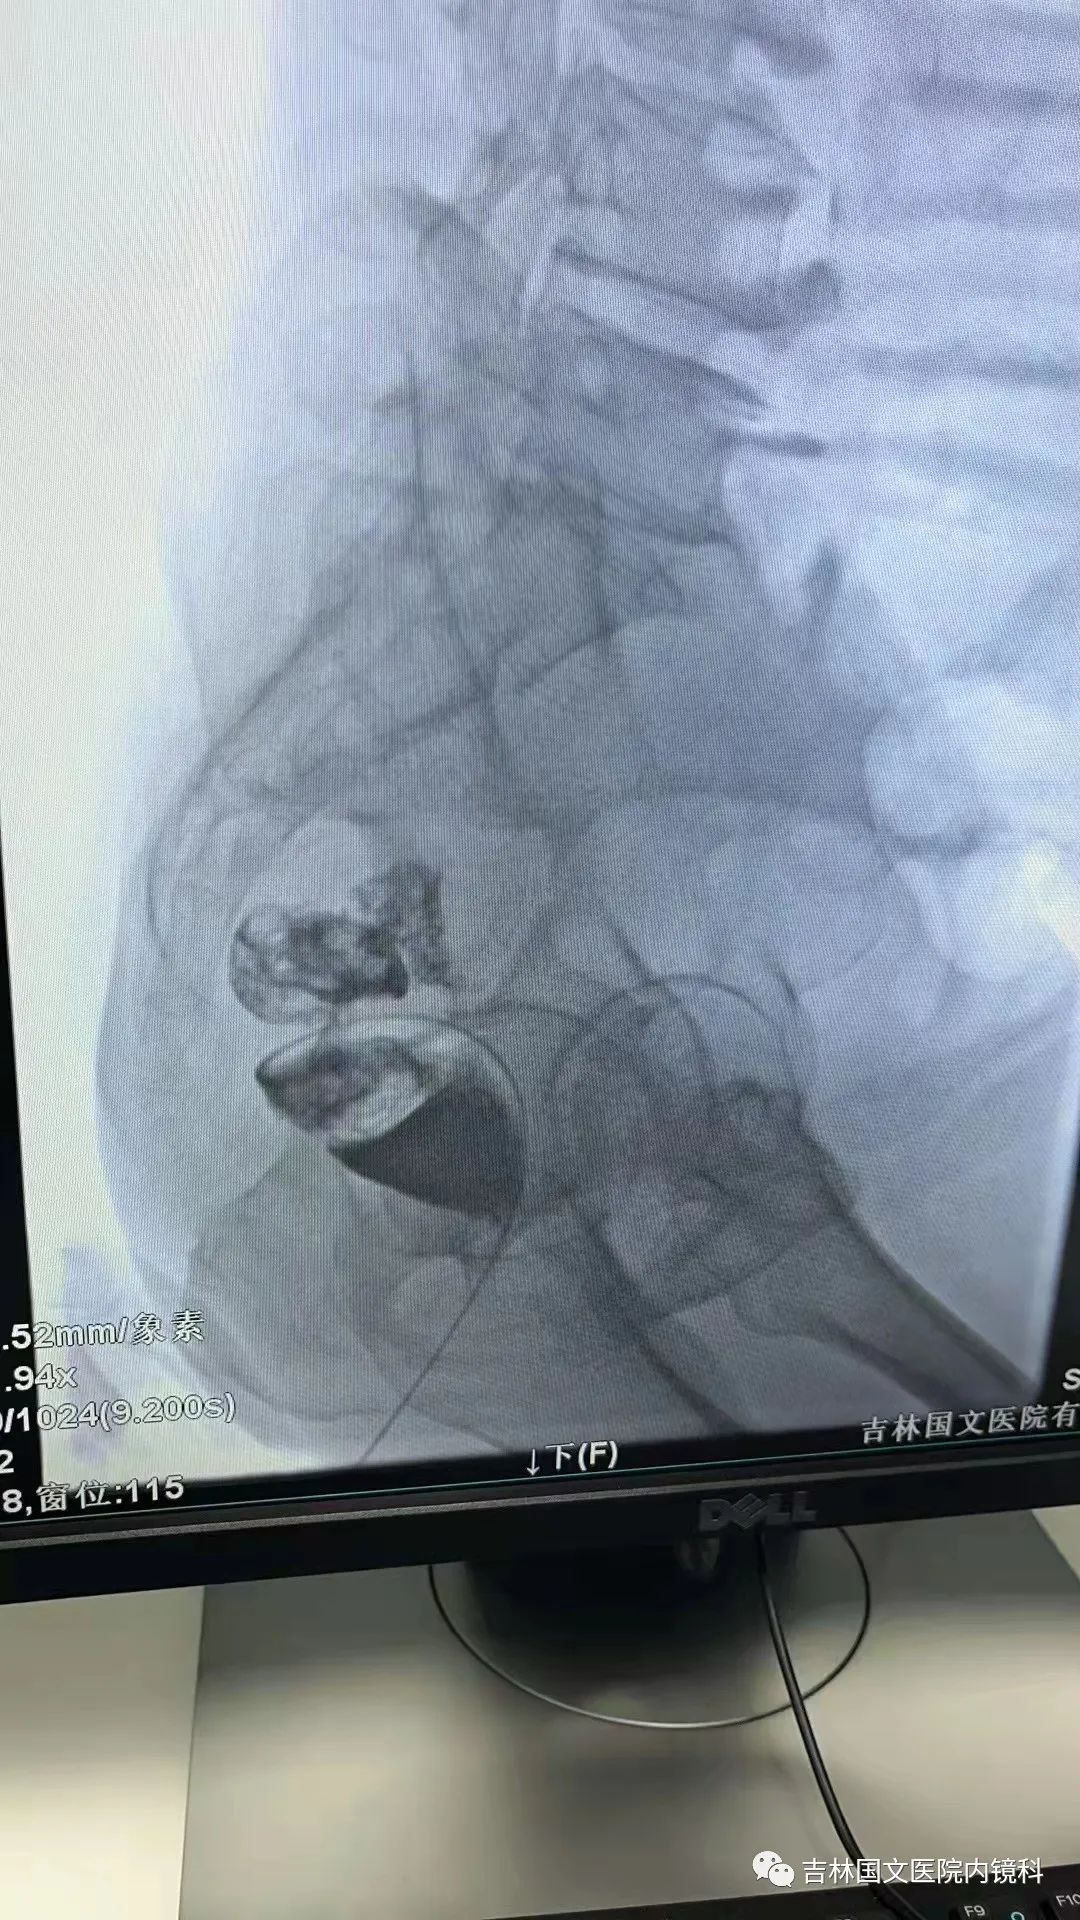

這是一位腸癌的患者,腫物生長在乙狀結(jié)腸,將腸腔堵得只剩一個小孔,糞便自然很難通過,腸梗阻的癥狀使患者十分難受,已多天未排氣排便,患者十分瘦削,開始侯主任未借助任何工具探查一番,結(jié)果就是腸道太迂曲了,實(shí)在無法順利將導(dǎo)絲置入,通過邢主任使用腸鏡在前面引路一直到達(dá)病變部位,這時候侯主任將帶有外套管的導(dǎo)絲從活檢口插入,外套管抵在小孔處,導(dǎo)絲順利進(jìn)入,第一步成功。第二步就是將支架順著導(dǎo)絲送入指定位置,又是一大難關(guān),導(dǎo)絲十分軟,缺乏支撐力,腸道的彎曲十分陡峭,一用力支架抵在腸道低處,患者痛感極強(qiáng),只能另想辦法,嘗試多次后,在兩位主任的豐富經(jīng)驗(yàn)和堅(jiān)持不懈的努力下,支架順利置入,為患者解除了痛苦。